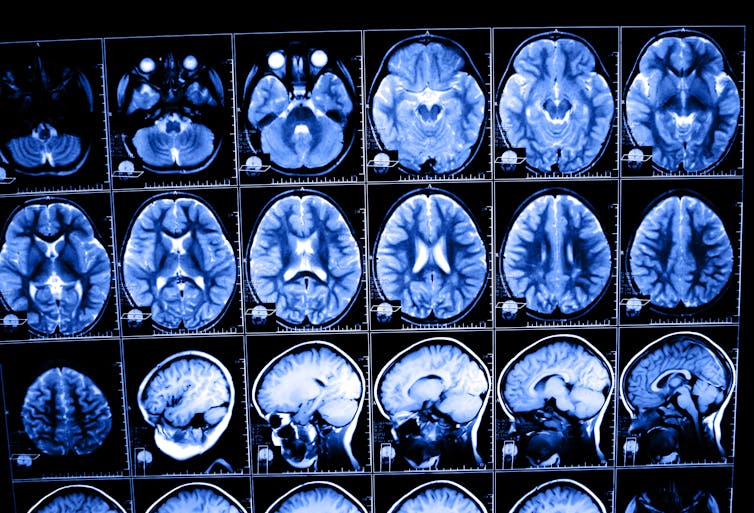

To measure brain temperature accurately, we need a very sensitive technique that can measure small temperature changes remotely, in real time, and with good spatial resolution. This is where near-infrared fluorescence comes in.

Fluorescence is a common technique for high-resolution, real-time imaging of cells. Researchers use contrast agents (dyes or nanoparticles) that emit visible light when illuminated. Some of these contrast agents change their fluorescence depending on the local temperature, acting as local, tiny, thermometers.

Using near-infrared fluorescent contrast agents, researchers have been able to see blood vessels in the brain through the skull in live mice – even tiny vessels no thicker than a few microns (one thousandth of a millimeter).

Some near-infrared nanoparticles are highly sensitive to changes in temperature. Combining them with wide-field fluorescence imaging, it is possible to measure the temperature of the brain temperature through the scalp and skull - no drill holes or inserted thermometers required.

My research used this technique to see, in real time, how brain temperature drops in live mice after drug administration. Near-infrared fluorescence thermometry can help us understand how brain temperature and neurological diseases are related – eventually leading to the application of temperature-based diagnosis in humans.